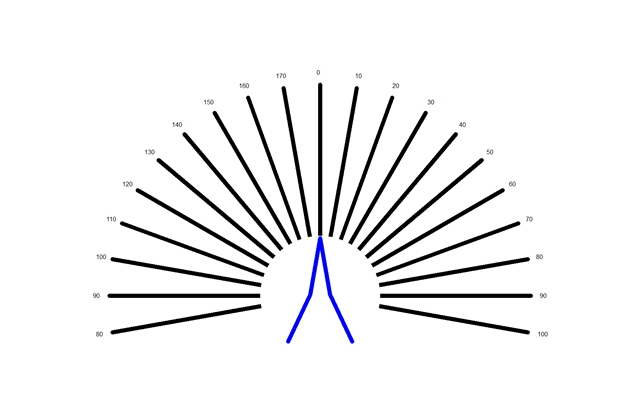

A:判斷自己有沒有散光,最簡單的方法是使用散光表來測試。散光表是一種簡單、方便的方法,但是它的準確度不是特別精確。在配鏡的情況下一般再用裂隙法,或者是交叉圓柱鏡法來精調散光的度數。散光表在網上可以看到,它類似於鐘錶的盤面,有12個數字。各個鏡線……